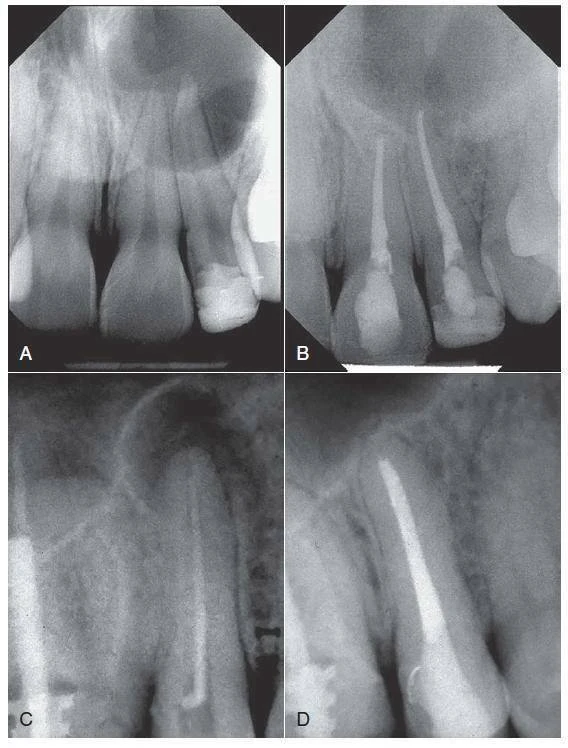

Rất nhiều các yếu tố trước và sau khi điều trị được cho là có liên quan tới kết quả điều trị nội nha. Những yếu tố này bao gồm tuổi và giới tính của bệnh nhân, vị trí của răng trên cùng hàm, độ rộng của ống tuỷ, các vật liệu băng ống tuỷ giữa các lần hẹn. Ví dụ như canxi hidroxit [Ca(OH)2]. Sự có mặt của các tổn thương xương cận chóp (ví dụ bệnh viêm nha chu chóp răng) được coi là một yếu tố tiên lượng làm giảm kết quả khả quan của điều trị tuỷ răng. Tuy nhiên, kích thước của tổn thương không phải là chỉ định để quyết định phẫu thuật nội nha. Hình 9-4 cho thấy hai trường hợp có tổn thương xương lớn được điều trị bằng phương pháp nội nha thông thường (từ trên xuống hay hướng thuận). Đối với những lần hẹn tiếp theo, răng đã không có triệu chứng, và kích thước tổn thương giảm hẳn cho cả hai ca.

Hình 9-4. Điều trị tuỷ trong trường hợp phá huỷ đáng kể cận chóp. A – Hình ảnh phim chụp trước điều trị của răng#8 và #9 cho thấy tổn thương lan rộng, răng không đáp ứng với thử lạnh. B – Hình ảnh phim chụp tái khám sau 2 năm cho thấy có tái tạo xương. Các ống tuỷ được tạo hình với dụng cụ cầm tay và các file máy và trám bít lèn bên bằng gutta-percha với chất AH Plus. C – Hình ảnh phim chụp trước điều trị của răng #4, cho thấy ống tuỷ trám bít, tổn thương cận chóp rộng và quan sát thấy trám bít chưa hoàn thiện. D – Hình ảnh phim chụp tái khám sau 2 năm cho thấy sự liền thương xương mà không điều trị phẫu thuật(A-B Courtsy Dr.M.Zehnder; C-D Courtesy Dr.E.Paque)